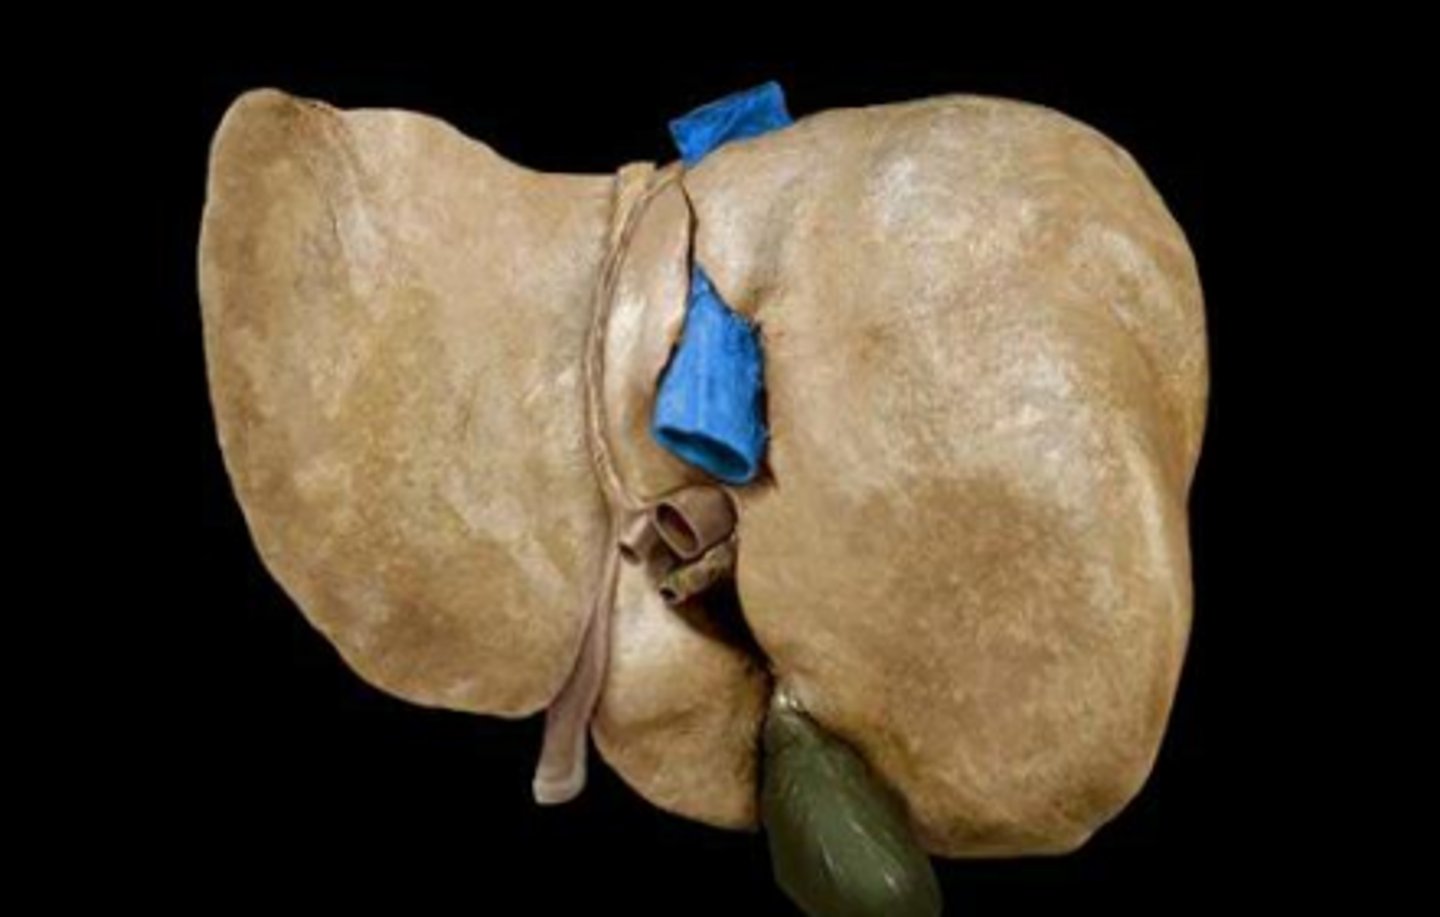

right lobe (of liver)

left lobe (of liver)

quadrate lobe (of liver)

caudate lobe (of liver)

diaphragmatic surface (of liver)

bare area (of liver)

not covered by peritoneum

inferior vena cava

round ligament of liver

porta hepatis

where the blood and lymph vessels, bile ducts, and nerves enter and leave the liver

hepatic artery proper

common bile duct

common hepatic duct

cystic duct

hepatic portal vein

gallbladder